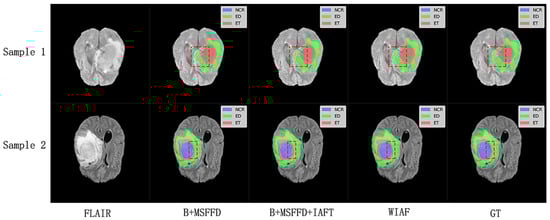

We selected two samples from each dataset of BraTS2020 and FeTS2022 for qualitative analysis using the methods proposed in this paper, specifically DiNTS, Swin UNETR, and Segformer3D. The results of the visualization are presented in Figure 5. To facilitate presentation, the 3D medical images will be displayed using a grayscale map of intermediate 2D slices along the depth dimension, with different tumor subregions distinguished by varying colors. Each tumor part is represented by a corresponding color. We chose the Flair sequence image as the primary reference point, while the Ground Truth (GT) indicates the segmented region of the label mask.

The visual results shown in Figure 9 further validate the quantitative findings of the ablation study. The model without IAFT and AWD-FD exhibits significant undersegmentation in the ED region compared to the ground truth labels, and the boundaries of the WT region are not defined with sufficient precision. After integrating the IAFT module, a significant improvement in tumor boundary segmentation was observed, highlighting the effectiveness of IAFT in modeling long-range dependencies and optimizing feature representations. Finally, the complete proposed model incorporating the AWD-FD module is the closest to the ground truth (GT). The AWD-FD module appears to further optimize segmentation by preserving finer details and improving contour accuracy, particularly in the ED region and at the interfaces between different tumor subregions. For example, the highlighted regions in Sample 2 indicate that the model successfully captured subtle infiltration patterns and reduced false positives within the tumor compared to the intermediate ablation stage. This qualitative evidence strongly supports the synergistic contribution of each proposed module toward achieving robust and accurate brain tumor segmentation.

Figure 5. Qualitative visualization of brain tumor segmentation results on selected axial slices from the BraTS2020 and FeTS2022 datasets. For each sample, the FLAIR MRI sequence is shown first, followed by the Ground Truth (GT) segmentation and predictions from our proposed WIAF model, DiNTS, Swin UNETR, and Segformer3D. In the segmentation masks, tumor subregions are color-coded as follows: enhancing tumor (ET) in red, peritumoral edema (ED) in green, and necrotic and non-enhancing tumor core (NCR/NET) in blue.